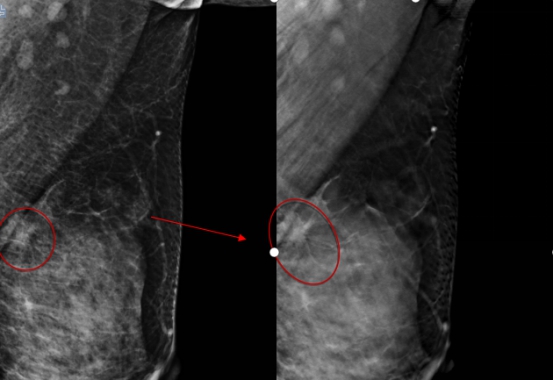

哈医大一院放射科主任陈颖教授介绍,由于李女士比较年轻,属于致密型乳腺,常规的乳腺钼靶摄片未发现明显的肿块,仅显示双乳增生及良性钙化。数字化乳腺断层摄影断层图像显示左乳外上象限长了一个5mm的结节,经放射线科钼靶室医生会诊发现,该结节有很大可能性是恶性的乳腺癌,因此建议李女士做活检或者入院手术治疗。术中冰冻切片发现该结节是乳腺原位癌,因此医生为她制定了保乳手术的治疗方案,目前正在康复中。术后,李女士特意打电话感谢放射线科的医生们帮助她及早地发现了这个病灶。

2020年末哈医大一院放射线科引进(HOLOGIC)数字化断层乳腺机,与传统的数字化钼靶乳腺机相比,能够最大限度地减少乳腺组织重叠,尤其是对年轻东方女性的致密型乳腺能够明显提高病灶检出率,大大降低了假阳性率及假阴性率。